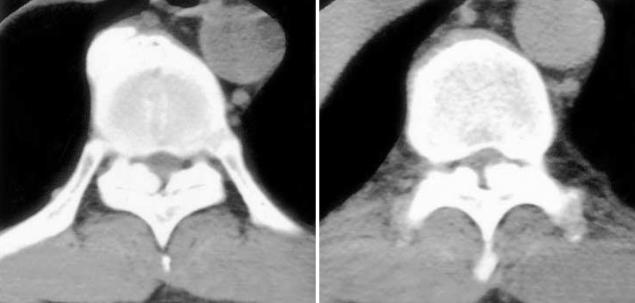

Acute neurologic deterioration is not a rare event in the surgical decompression for thoracic spinal stenosis. We report a case of transient paraparesis after decompressive laminectomy in a 50-yr-old male patient with multi-level thoracic ossification of the ligamentum flavum and cervical ossification of the posterior longitudinal ligament. Decompressive laminectomy from T9 to T11 was performed without gross neurological improvement. Two weeks after the first operation, laminoplasty from C4 to C6 and additional decompressive laminectomies of T3, T4, T6, and T8 were performed. Paraparesis developed 3 hr after the second operation, which recovered spontaneously 5 hr thereafter. CT and MRI were immediately performed, but there were no corresponding lesions. Vascular compromise of the borderlines of the arterial supply by microthrombi might be responsible for the paraparesis.

在胸椎椎管狭窄症的手术减压中,急性神经功能恶化并非罕见事件。我们报告了一例50岁男性患者,该患者患有多节段黄韧带骨化和颈椎后纵韧带骨化,在进行减压性椎板切除术后出现短暂性截瘫。对T9至T11进行了减压性椎板切除术,但神经功能未得到明显改善。首次手术后两周,进行了C4至C6的椎板成形术以及T3、T4、T6和T8的额外减压性椎板切除术。第二次手术后3小时出现截瘫,5小时后自行恢复。立即进行了CT和MRI检查,但未发现相应病变。微血栓对动脉供应边界的血管压迫可能是导致截瘫的原因。